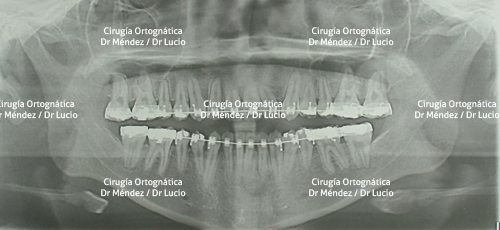

RETROGNASIA E HIPOPLASIA DEL MENTÓN Paciente operado de avance de mandíbula y mentoplastia de avance |

||